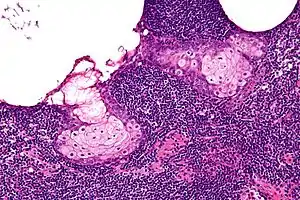

| High magnification micrograph of a sebaceous lymphadenoma. H&E stain. | |

Sebaceous lymphadenoma is a tissue diagnosis, e.g. salivary gland biopsy.

It may be confused with a number of benign and malignant neoplasms, including Warthin tumour, mucoepidermoid carcinoma and sebaceous lymphadenocarcinoma.[2]